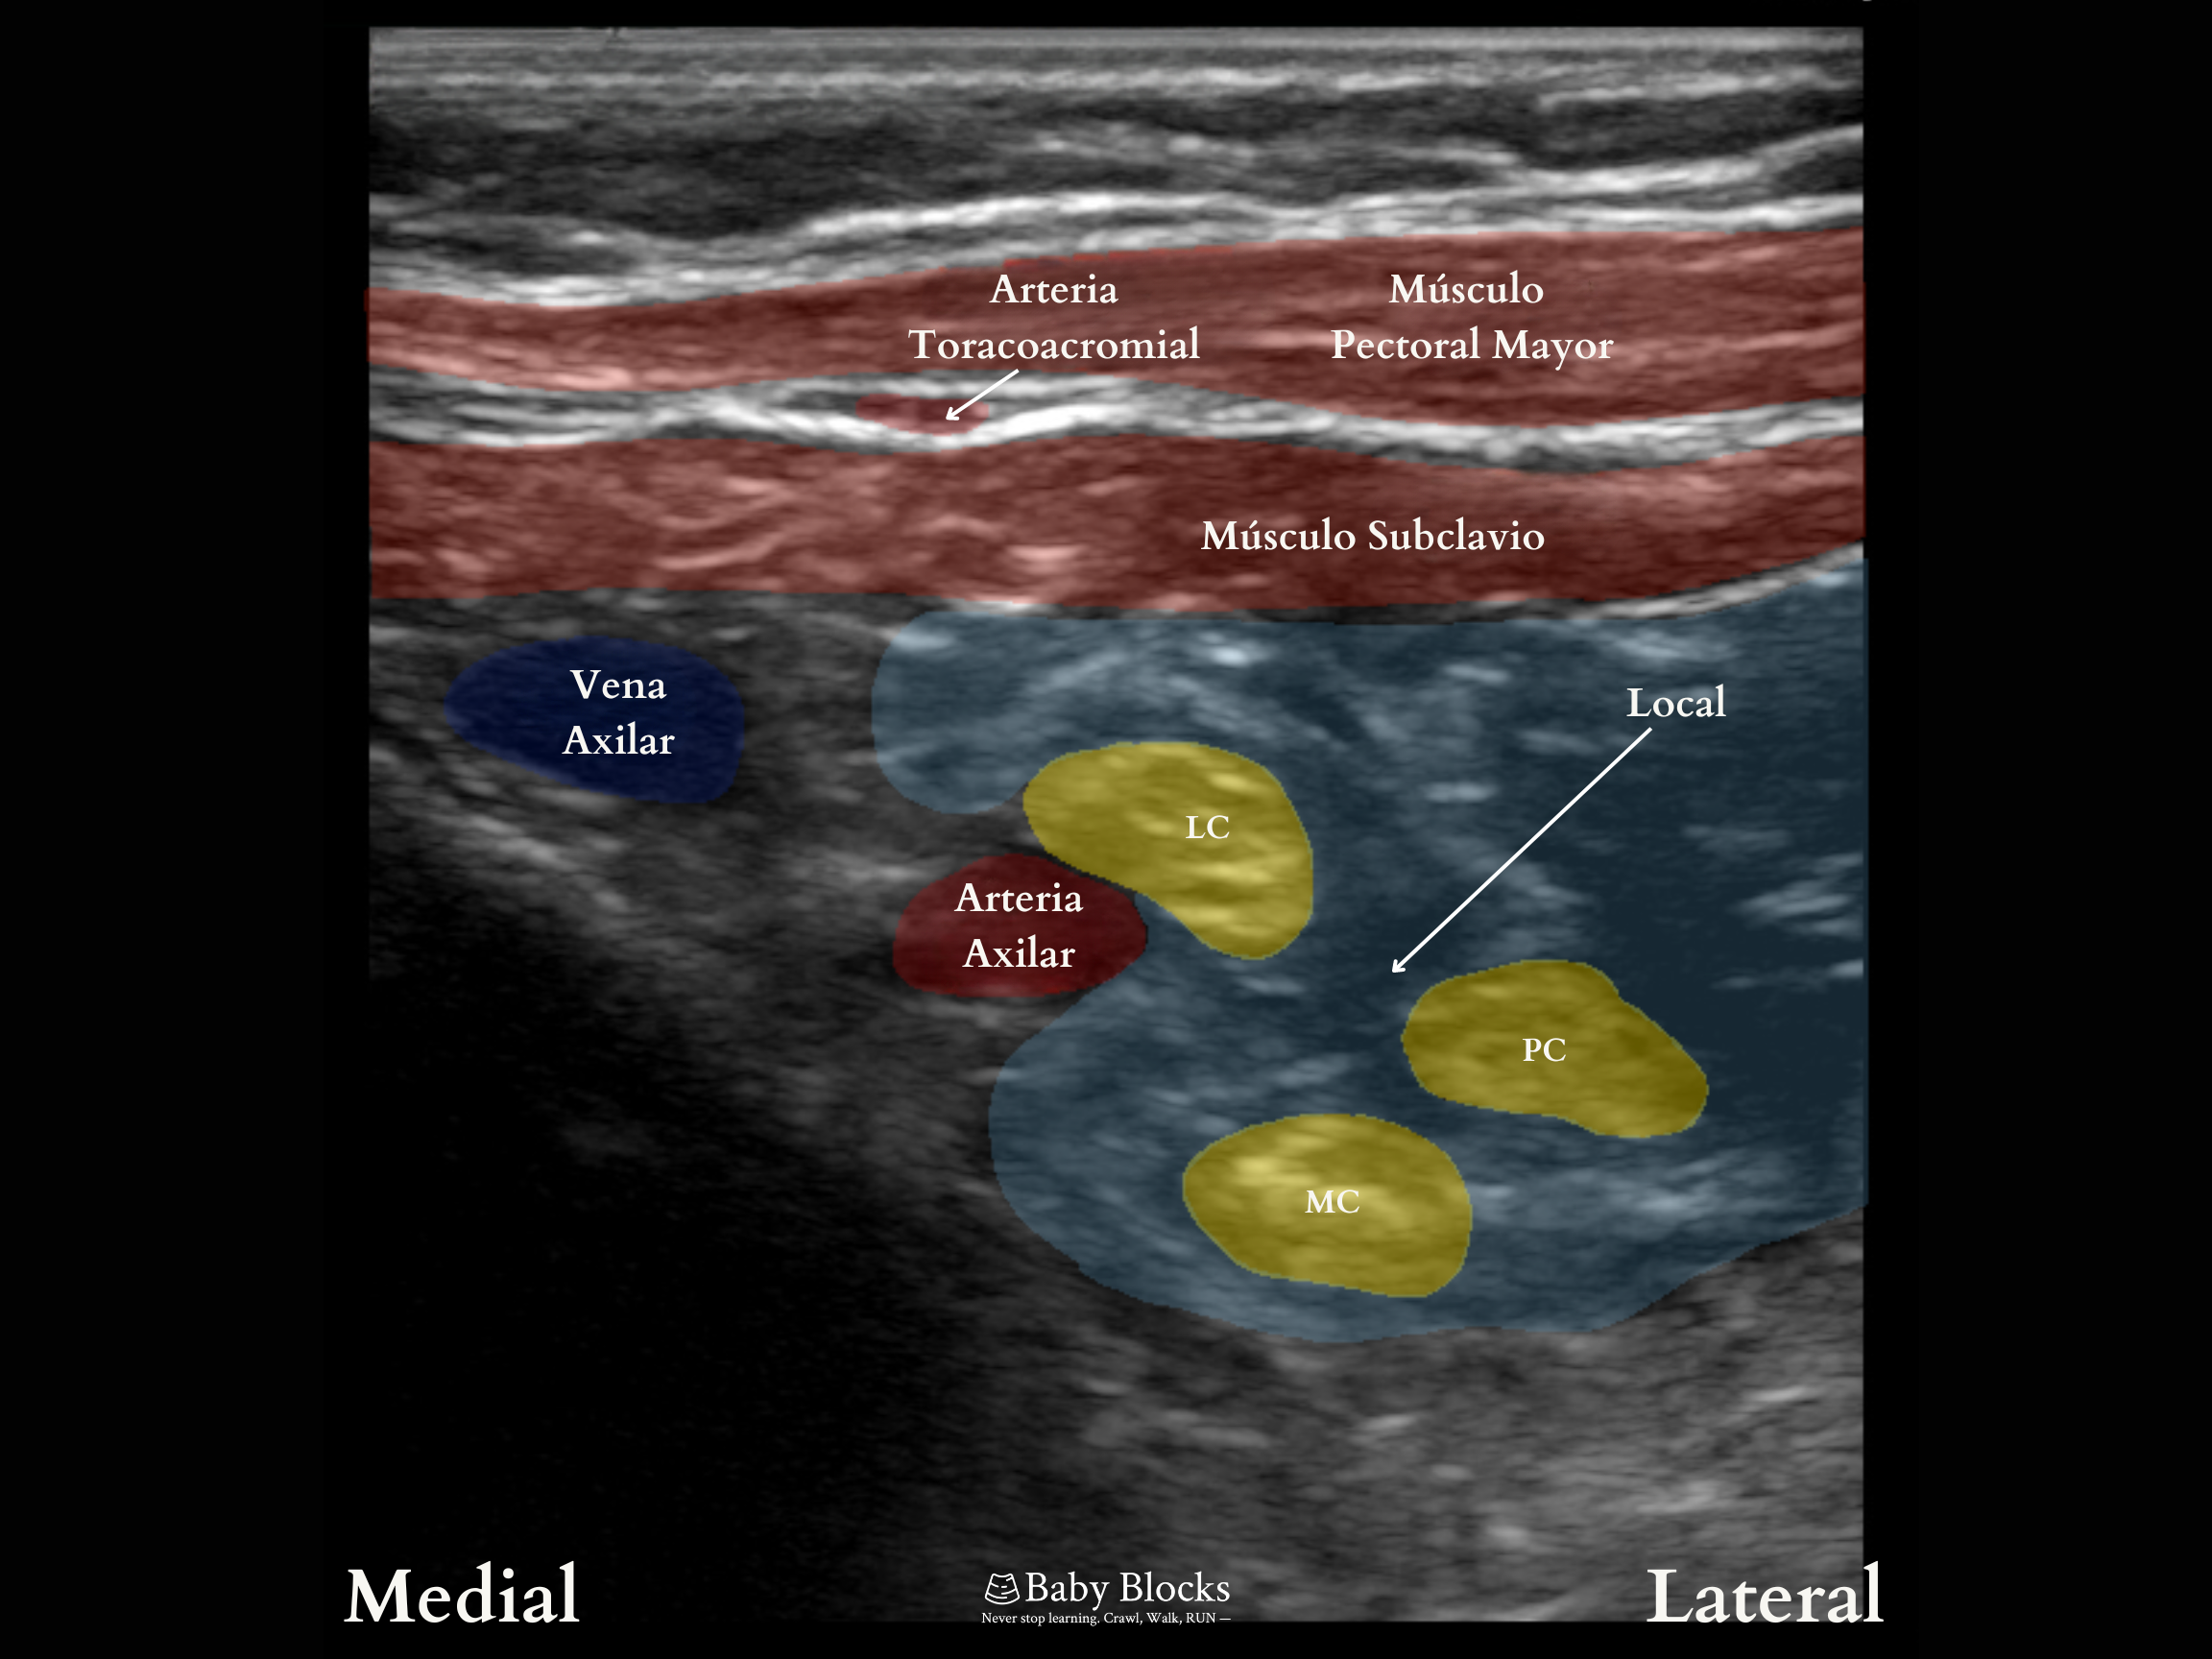

Consideraciones: Esta es una variación del abordaje lateral-sagital del bloqueo del plexo braquial a nivel infraclavicular. En este enfoque, se deposita el anestésico local un poco más medial en el espacio costoclavicular, con el transductor sostenido en paralelo a la clavícula. Es crucial visualizar e identificar la ubicación de los tres cordones del plexo, los cuales están consistentemente posicionados y agrupados justo lateral a la arteria, en una relación nervio-arteria algo similar a la vista en el bloqueo supraclavicular, pero realizada inferior a la clavícula. En algunos pacientes pediátricos, este enfoque también puede ofrecer más espacio para manipular la aguja.

Comience con la sonda directamente sobre el punto medio de la clavícula y deslícela en dirección lateral y caudal para salir justo de su superficie ósea. Posteriormente, incline ligeramente el transductor en dirección cefálica hasta visualizar la arteria y vena axilar, así como los cordones en posición lateral. Optimice la imagen con pequeños ajustes de rotación en sentido horario y antihorario del transductor, hasta lograr una visualización en sección transversal de la arteria.

La punción se realiza en plano, con una dirección de lateral a medial. La posición ideal de la punta de la aguja es en el centro de los 3 cordones, justo entre los cordones lateral y posterior, pero con cuidado de no avanzar hacia el cordón medial.

Ocasionalmente, se identifica la vena cefálica o la arteria toracoacromial atravesando la trayectoria deseada de la aguja. Si este es el caso, se puede mover el transductor hacia medial y/o tilting cefálico.

Imágenes de Ultrasonido